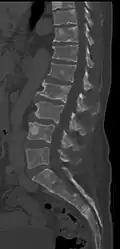

The diagnostic examination of a person with suspected multiple myeloma typically includes a skeletal survey. This is a series of X-rays of the skull, axial skeleton, and proximal long bones. Myeloma activity sometimes appears as "lytic lesions" (with local disappearance of normal bone due to resorption) or as "punched-out lesions" on the skull X-ray ("raindrop skull"). Lesions may also be sclerotic, which is seen as radiodense.[76] Overall, the radiodensity of myeloma is between −30 and 120 Hounsfield units (HU).[77] Magnetic resonance imaging is more sensitive than simple X-rays in the detection of lytic lesions. An MRI may supersede a skeletal survey, especially when vertebral disease is suspected. Occasionally, a CT scan is performed to measure the size of soft-tissue plasmacytomas. Nuclear Medicine Bone scans are typically not of any additional value in the workup of people with myeloma (no new bone formation; lytic lesions not well visualized on nuclear bone scan).

CT scan of the lower vertebral column in a man with multiple myeloma, showing multiple osteoblastic lesions: These are more radiodense (brighter in this image) than the surrounding cancellous bone, in contrast to osteolytic lesions, which are less radiodense. -